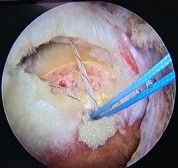

Khâu phục hồi gân cơ CX rách theo kỹ thuật khâu gân một hàng Mason-Allen cải biên của hai tác giả Scheibel và Habermeyer kết hợp với ứng dụng giải phẫu 20:

- Mũi khâu nằm ngang được tiến hành thực hiện trước với hai mũi khâu của hai đầu chỉ đi từ phía bề mặt khớp của CX, xuyên qua gân đến bề mặt khoang dưới MCV, KC giữa hai mũi khâu là khoảng 10mm, và KC từ bờ gân đứt đến vị trí mũi khâu khoảng 10mm.

- Mũi khâu thẳng đứng được thực hiện sau, mũi khâu này sẽ đi qua vị trí ở giữa và cách khoảng 1-2 mm ở phía trong so với mũi khâu nằm ngang.

Hình 2.24. Trình tự khâu gân theo phương pháp Mason-Allencải biên

* Nguồn: ảnh chụp trong mổ của BN Phan Quang A, mã số bệnh án 19945554